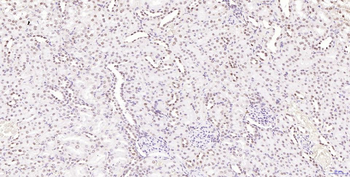

100 μl, 200 μl, 50 μl - LATS2 Rabbit Polyclonal Antibody [orb6306]Featured

IF, IHC-Fr, IHC-P, WB

Human, Mouse, Rat

Bovine, Canine, Equine, Gallus, Rabbit

Rabbit

Polyclonal

Unconjugated

100 μl, 200 μl, 50 μl - Featured